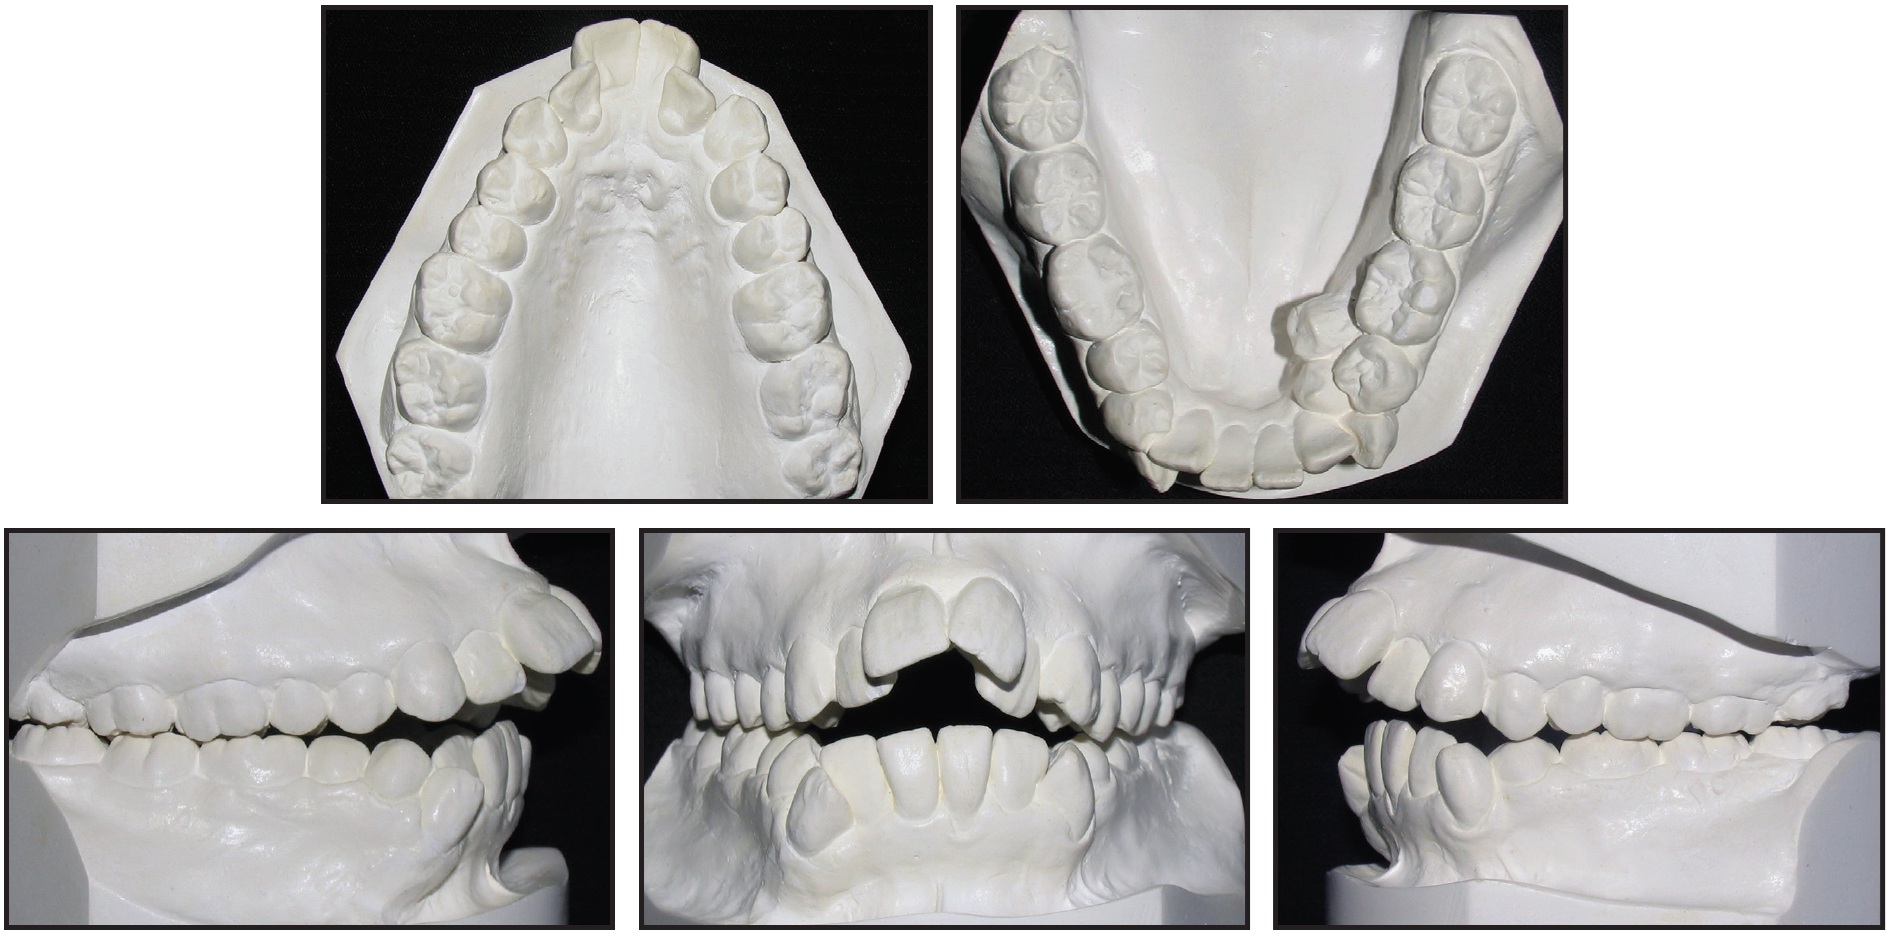

The treatment objectives were achieved, in part due to perfect patient cooperation with the headgear and intraoral elastics and optimal oral hygiene. The extractions in the upper arch allowed the anterior teeth to be retracted, facilitating bite closure and overjet reduction (Fig. 5A). Profile convexity was improved, as was lip closure. When the patient smiled, an expanded maxillary arch and full upper-incisor-crown display were evident.

Fig. 5 A. Patient after 30 months of treatment.

Post-treatment records showed bilateral Class I molar and canine relationships. Both dental midlines were reasonably well aligned with the facial midline, and optimal overjet and overbite were achieved. Cephalometric analysis revealed no change in ANB (Table 1). In addition, no significant clinical changes in the vertical measurements were noted, indicating that the mechanics were able to control vertical movement of the posterior teeth. The upper incisors were extruded and retroclined, and the lower incisors were slightly proclined and extruded (Fig. 5B).

Fig. 5 (cont.) A. Patient after 30 months of treatment. B. Superimposition of pre- and post-treatment cephalometric tracings.

Soft-tissue analysis showed an improvement in the lower-third convexity by backward positioning of the lower lip in relation to the Holdaway line, improving lip closure at rest. The panoramic radiograph confirmed proper root parallelism. Supporting tissues appeared healthy, and no root resorption was noted.

The occlusion remained stable one year after treatment (Fig. 6).

Fig. 6 Patient one year after treatment.